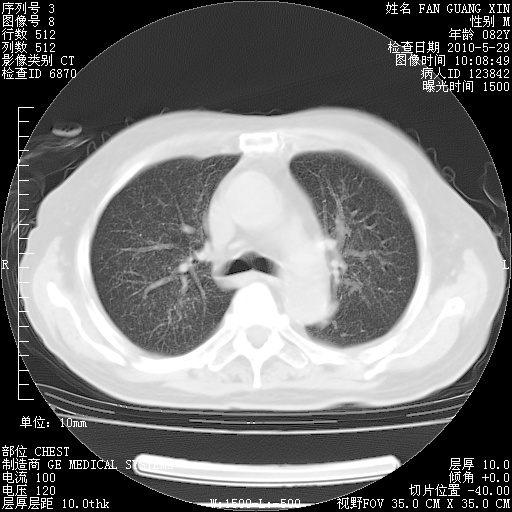

再治疗10天后的肺部CT

从白细胞总数和中性比例看好像合并感染。肺部纹理好像比上次多,支气管炎?其他感染?

阅读此次胸部CT,肺间质渗出性改变较入院时有吸收。目前从体温、白细胞、中性分叶明显增高,肯定存在细菌感染(发生医院感染哦,若无消化道及泌尿系统等感染的依据,肺部感染可能大)。若你院头孢哌酮舒巴坦钠耐药率较高,同意你的方案,若48小时体温仍高,可考虑使用碳青霉稀类抗菌药物,同时可予超声雾化、注意滴数时加大液体量。白蛋白33.30g/L较低哦,需加强营养等支持治疗。